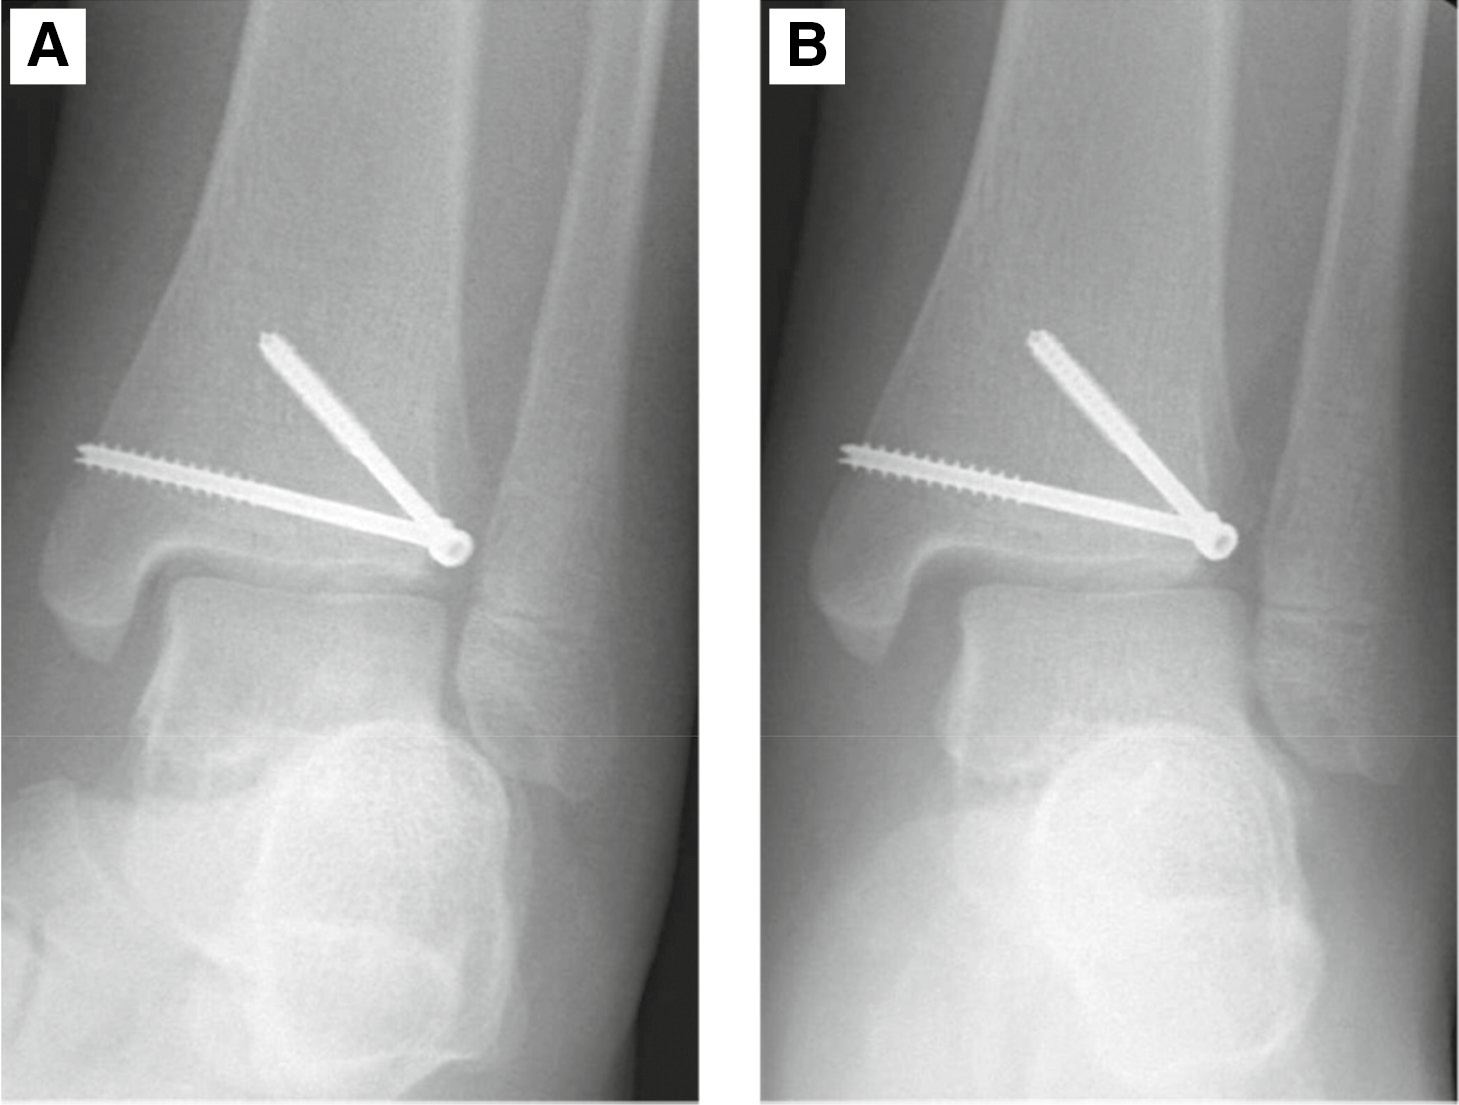

At his 6-week postoperative visit, he had healed well with good passive ankle range of motion. X-ray showed intact suture button without syndesmosis disruption (Figure 6). At the 12-week postoperative visit, he had slight soreness around the ankle with compression. He had full inversion/eversion of the ankle but mild stiffness in flexion and extension. He was able to ambulate with heel-toe gait and was able to hop on one leg. Patient started at-home rehabilitation for strengthening. He was doing well at 9-month follow-up visit and back to regular activities without pain.

Figure 6. (A) Postoperative AP and (B) lateral radiographs of the ankle.

jposna2022553_fig6.jpg